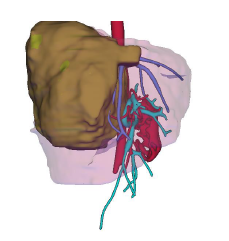

门诊经常会遇到因为体检发现肝血管瘤来咨询的朋友。最近就有一位女士因为右上腹明显胀痛一月,发现肝巨大血管瘤就诊。腹部增强CT可见血管瘤最大径达20cm(图1、2)。考虑肝巨大血管瘤伴有明显不适症状,需要行手术切除,术后患者腹部不适完全缓解。

图2:术前影像三维重建可见右肝巨大血管瘤(褐色)